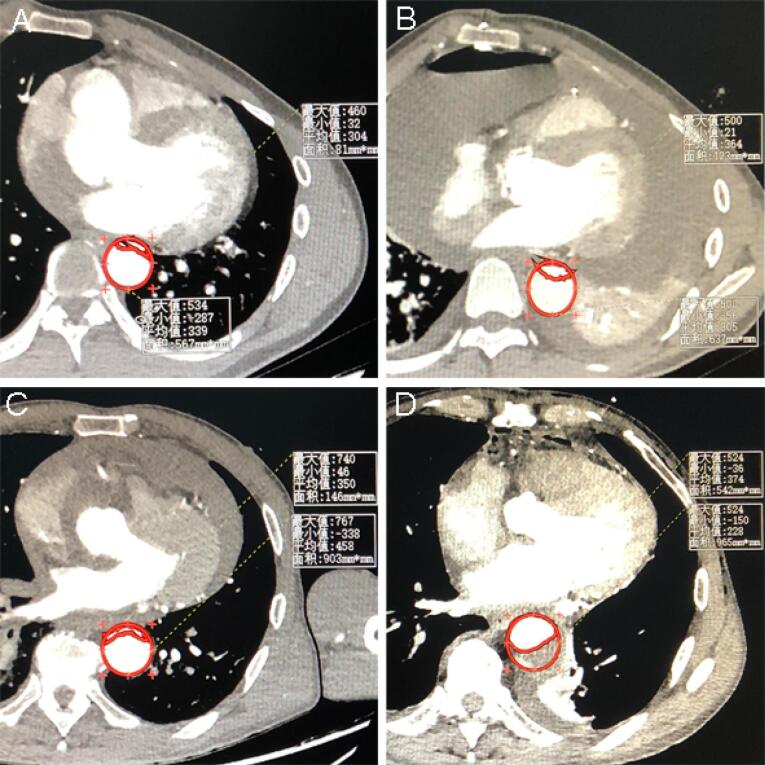

Introduction: Acknowledging lacking of recognition on postoperative aortic remodeling by intraoperative transition of cannulation perfusion mode during the open repair surgery of DeBakey type I acute aortic dissection (AAD), this study aims to investigate the effect of interactive cannulation strategy on the maximum false lumen area (MFLA) ratio.

Methods: A total of 321 AAD patients were retrospectively reviewed from March 2017 to March 2023, of which 166 patients receiving peripheral cannulation (PC, right axillary and femoral artery) and 155 patients receiving peripheral-to-centric cannulation (PCC, transition from right axillary and femoral artery to one branch of the tetrafurcated graft). The primary outcome was postoperative MFLA ratio in descending thoracic aorta. Secondary outcomes were postoperative inflammation response and anaerobic metabolism, hepatorenal dysfunction, and the ostium condition of branch artery of abdominal aorta involved by false lumen.

Results: There was a lower postoperative MFLA ratio in PCC group than that in PC group, respectively (0.36±0.11 vs. 0.44±0.13, P<0.001). The abdominal branch arteries involved by false lumen was also deceased in PCC group. There was also a lower serum inflammation response (24 hours, hr-CRP: 111.8±14.1mg/L vs. 116.8±15.0mg/L, P=0.002; IL-6: 104.4±49.9pg/ml vs. 124.0±50.1pg/ml, P<0.001), anaerobic metabolism (8 hours, lactate: 8.3±1.5mmol/L vs. 8.8±1.6mmol/L, P=0.002), impaired liver function (15.5% vs. 39.8%, P<0.001) and need for renal replacement therapy (10.3% vs. 20.5%, P=0.012) in PCC group than those in PC group.

Conclusion: Interactive cannulation with prompt transition from peripheral artery to centric perfusion during surgical repair of AAD was associated with the reduction of MFLA and hepatorenal dysfunction.